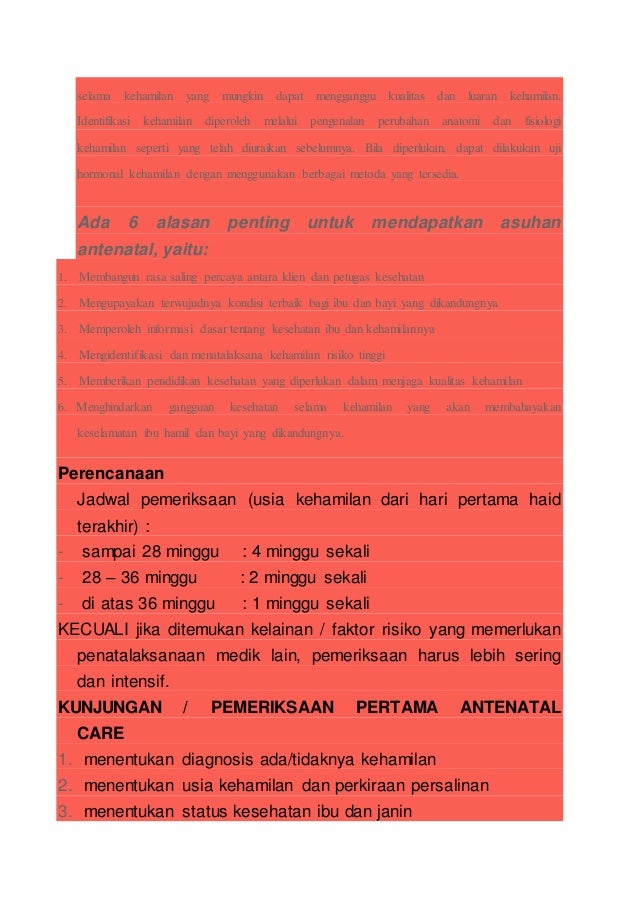

Tujuan Pemeriksaan K4

Tujuan Pemeriksaan K4

Menentukan Periode Dan Usia Kehamilan Ppt Download

Menentukan Periode Dan Usia Kehamilan Ppt Download

Hubungan Karakteristik Sosial Ekonomi Tingkat Pendidikan Tingkat Penghasilan Dan Jenis Pekerjaan Ibu Hamil Usia Kehamilan 36 Minggu Dengan Frekuensi Kunjungan Anc Antenatal Care Di Poli Kia Puskesmas Dinoyo Kota Malang

Hubungan Karakteristik Sosial Ekonomi Tingkat Pendidikan Tingkat Penghasilan Dan Jenis Pekerjaan Ibu Hamil Usia Kehamilan 36 Minggu Dengan Frekuensi Kunjungan Anc Antenatal Care Di Poli Kia Puskesmas Dinoyo Kota Malang

Infografis Timeline Periksa Kandungan Untuk Ibu Hamil

Infografis Timeline Periksa Kandungan Untuk Ibu Hamil

Asuhan Pada Kehamilan Trimestar 3 Tujuan Pemeriksaan Jadwal Pemeriksaan Kehamilan Usia Kehamilan Pengertian Dampak Tidak Memeriksakan Kehamilan Daftar Ppt Download

Asuhan Pada Kehamilan Trimestar 3 Tujuan Pemeriksaan Jadwal Pemeriksaan Kehamilan Usia Kehamilan Pengertian Dampak Tidak Memeriksakan Kehamilan Daftar Ppt Download